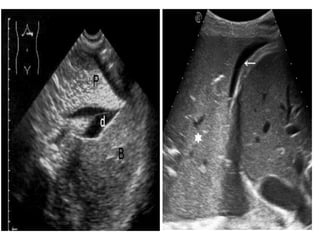

»ECOGRAFIA:

→La energía ultrasónica se disipa en el aire por

ello la ecografía no ayuda al estudio del

parénquima pulmonar

→La ecografía endobronquial permite la

identificación y localización de alteraciones

cercanas alas paredes de las vías respiratorias o

en el interior del mediastino

→Detecta y localiza anomalías pleurales y suele

emplearse como guía para la extracción de

liquido pleural (toracocentesis)